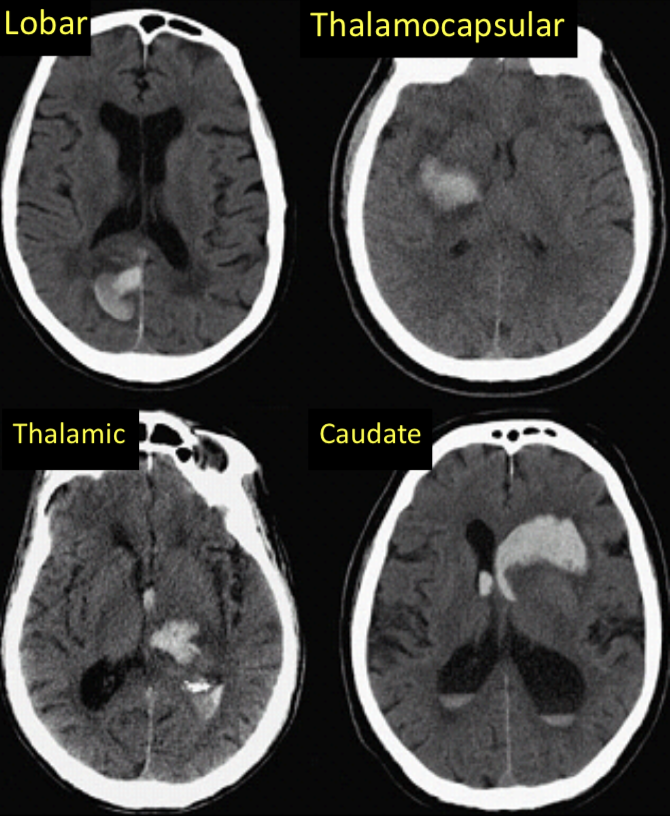

ICH

-types intraxial hemorraghe